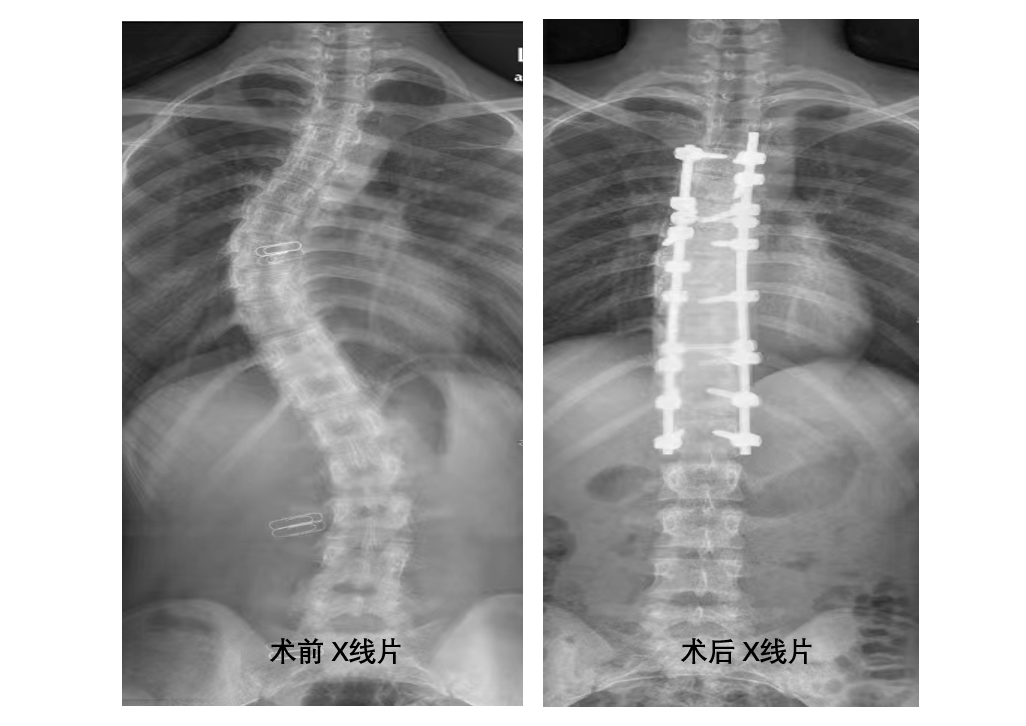

術(shù)前、術(shù)后x線片

“初見小萍是去年, 16歲的小姑娘雙肩明顯不平衡,X線片顯示脊柱側(cè)凸,主胸彎曲36°,雖然屬于典型的青少年型特發(fā)性脊柱側(cè)凸,但還未達(dá)到手術(shù)指征,我們建議她進(jìn)行功能鍛煉,并觀察。沒想到,她的病情進(jìn)展速度比較快,一年就長了十來度,必須要進(jìn)行手術(shù)治療?!迸输摽傖t(yī)院骨科主任馬剛介紹說,脊柱側(cè)凸矯形手術(shù)是脊柱外科領(lǐng)域難度最大、風(fēng)險(xiǎn)最高的手術(shù)之一,稍有不慎便會(huì)造成雙下肢截癱,大小便失禁。

小萍入院后,完善了相關(guān)檢查, X線片顯示主胸彎曲47°,且她的側(cè)凸分型為lenke 1BN型脊柱側(cè)彎。小萍胸椎椎弓根發(fā)育異常,加之骨骼基本發(fā)育完全,骨質(zhì)僵硬……都增加了手術(shù)的難度。 “ 要達(dá)到矯形目的,需要進(jìn)行胸4~腰1長階段椎弓根螺釘固定,患者椎弓根發(fā)育較小,胸椎緊鄰胸主動(dòng)脈和靜脈,椎管內(nèi)為胸脊髓,如果置釘出現(xiàn)問題,后果將難以想象。”“術(shù)前,我們必須根據(jù)CT影像規(guī)劃好植入螺釘?shù)闹睆礁嵌龋贫ê眯舻捻樞? 術(shù)中,必須請(qǐng)麻醉科配合進(jìn)行術(shù)中喚醒,同時(shí)準(zhǔn)備好自體回收血。”…… 脊柱外科手術(shù)團(tuán)隊(duì)反復(fù)研究病情, 多次進(jìn)行術(shù)前討論、制定手術(shù)規(guī)劃。

充分的術(shù)前準(zhǔn)備就緒,在麻醉科的大力支持和配合下,骨科脊柱外科手術(shù)團(tuán)隊(duì)順利完成了后路減壓截骨矯形+椎弓根釘棒系統(tǒng)內(nèi)固定手術(shù),手術(shù)歷時(shí) 5  小時(shí)。術(shù)后復(fù)查X線片,側(cè)彎矯形成功。